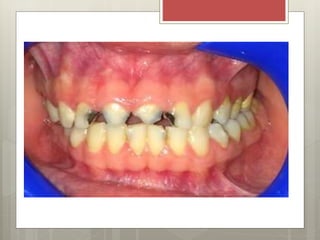

IMÁGENES INTRAORALES